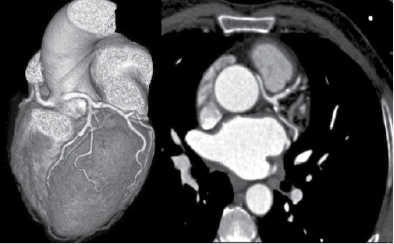

At Nizam’s Institute of Medical Sciences (NIMS), Hyderabad, 770 patients underwent CT-conventional coronary angiography (CAG), on 128-slice single source MDCT (SOMATOM Definition AS ± SEIMENS) during the last 3 years (unpublished data). On analysis, coronary artery anomalies were found in 23 patients (3%). Their ages ranged from 25 to 82 years. Majority of the cases were in 51 to 60 years age group. Among them, 17 were males. The most common anomaly seen was high take-off of coronary arteries, seen in 10 cases. Of them, 2 were having high origin of right coronary artery (RCA) (Fig. 1), 7 were having high origin of left main coronary artery (LMCA) and one was having high origin of both coronary arteries with acute kink at the origin of RCA. Anomalous origin of coronary artery from opposite sinus was seen in 8 cases (Figs. 2-5). RCA from left coronary sinus with interarterial course between aorta and right ventricular outflow tract was seen in 5 cases. Anomalous origin of left coronary artery (LCA) from right coronary sinus with interarterial course between aorta and right ventricular outflow tract was seen in 2 cases. Anomalous origin of left circumflex artery (LCx) from right coronary sinus with retroaortic course was seen in 1 case (Fig. 6). Separate ostia for left anterior descending artery (LAD) and LCx was noted in 3 patients (Figs. 7 and 8). Shepherd crook deformity of proximal segment of RCA was seen in 1 patient. Super-dominant RCA with absent LCx was seen in 1 patient (Fig. 9).

Figure 4. Origin of RCA and LCA from left coronary sinus in a patient aged 35/M.

Figure 5. Origin of RCA and LCA from left sinus of Valsalva with interarterial course of RCA in a patient aged 25/M.

Origin of coronary artery or branch from the opposite or noncoronary sinus is another anomaly that is commonly observed. These anomalies are classified into 4 types. One is interarterial course between aorta and pulmonary artery. Second one is retroaortic course. Third is prepulmonic and septal or subpulmonic course. The interarterial course is clinically important as it is associated with sudden death.5 Fujimoto et al, in their series of 5,869 cases, noted that 29 cases had opposite coronary sinus and in 27 of these cases RCA arose from left coronary sinus.4 All these cases had interarterial course. It is reported that 30% of these have sudden cardiac death. Anomalous origin of coronary artery from opposite sinus was seen in 8 cases accounting for 1.04%. RCA from left sinus were 5 and LCA from right coronary sinus were 2 with interarterial course. In 1 case, LCx was arising from right coronary sinus with retroaortic course.

Finocchiaro et al in their study of 5,100 cases found anomalous coronary arteries in 0.6%. Anomalous left coronary artery (ALCA) arising from right sinus of Valsalva with interarterial course (11) and RCA originating from left sinus of Valsalva (RACA) with interarterial course (11) were most commonly found. ALCA arising from pulmonary artery was present in 7 cases and in 1 case, the LCA arose from noncoronary sinus.6 In a similar study by Nguyen, the incidence of anomalies was 47 out of 9,572 cases (0.49%). LCx from RCA/right sinus of Valsalva was seen in 31.9%. High take-off of RCA was seen in 23.4%, RCA from left coronary sinus was noted in 17% and LCA from right coronary sinus was seen in 10.6%.7 Approximately 1.04% of our cases had anomalous origin of coronary artery (5 RCA and 2 LCA, and in 1 LCx was originating from right coronary sinus with retroaortic course).